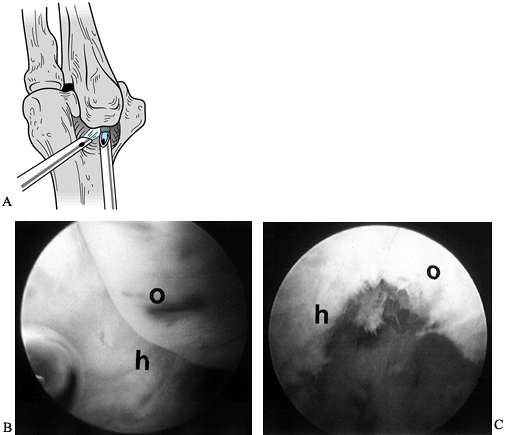

Initially debride the synovitis

posteriorly in order to improve visualization. Then use a burr or

shaver to debride the posterior olecranon osteophyte (Fig. 82.14).

Figure 82.14. A:

A diagram of debridement of a posteromedial olecranon osteophyte. The

camera is in the posterolateral portal, with the burr in the straight

posterior portal. B: Arthroscopic view of the posterior compartment with olecranon osteophyte (o) and humerus (h). C: Arthroscopic view after debridement of the olecranon osteophyte. -

The question is how much of the osteophyte should be removed. When this operation was initially developed (1),

a relatively generous excision of the osteophyte was recommended. In

more recent years, however, less aggressive excision has been adopted

because excessive debridement increases the stress on the ulnar

collateral ligament. Typically 4 to 5 mm is removed, or enough to

debride the loose fragments and prevent further impingement. If there